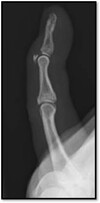

Q

What pathology is shown here?

Osteosarcoma